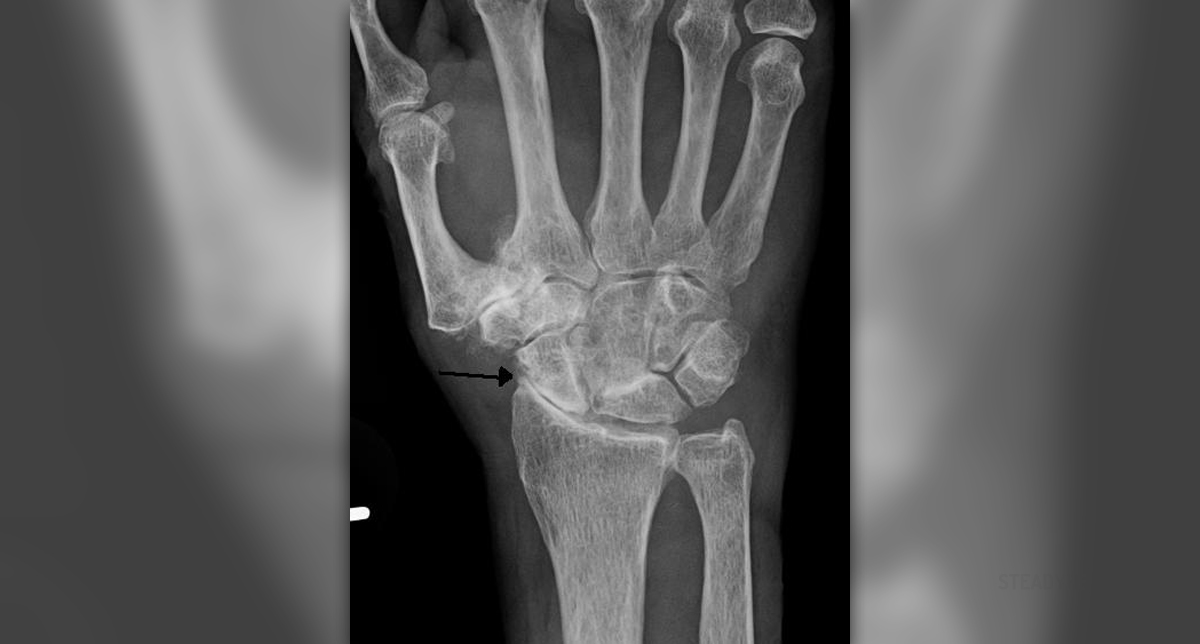

Osteopenia

Osteopenia is a medical condition which features with loss of bone density. This means that bones become thinner. Luckily the bone loss in osteopenia is minor comparing to osteoporosis. Nonetheless, patients who have been diagnosed with osteopenia have to pay attention to this condition since it eventually leads to osteoporosis. Osteopenia can be defined as introduction to osteoporosis.

The diagnosis can be set after Dexa scans. This scan measures the bone density in hips and spine.